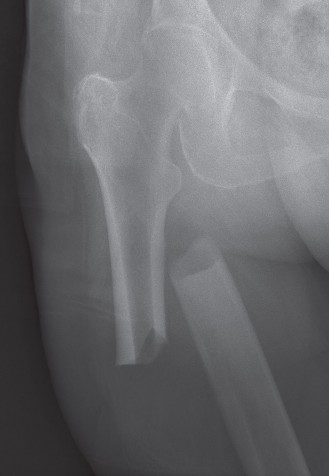

Image